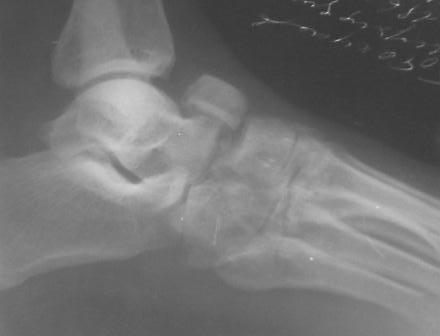

Уважаемый Абдурашид, с большой долей вероятности можно говорить о том, что в результате ДТП пациент плучил вывих в суставе Шопара с переломом одной из костей, скорее всего, действительно ладьевидной. Подтвердить это можно, попытавшись сделать более качественные ргр плюс снимки косым лучом для идентификации передних отделов таранной кости и таранно-ладьевидного сустава. Как я понимаю, выполнить КТ для данного пациента маловероятно. Тогда попробуйте воспользоваться таким старым, но в ряде случаев эффективным методом, как сравнительные Ргр здоровой конечности. Если Вы подтвердите д-з вывиха, а скорее да, по сохраняющемуся подвывиху, да иначе и сложно себе представить, как произошло такое смещение фрагмента, и, учитывая срок с момента травмы, Вам придётся выполнить артродез таранно-ладьевидного и, скорее всего, пяточно-кубовидного сочленений. С уважением, Волна

По данному случаю, оказалось 3 месяца назад было произведена Р-графия в райбольнице, но больной предпочел лечится у табиба. Присылаю первичные снимки.